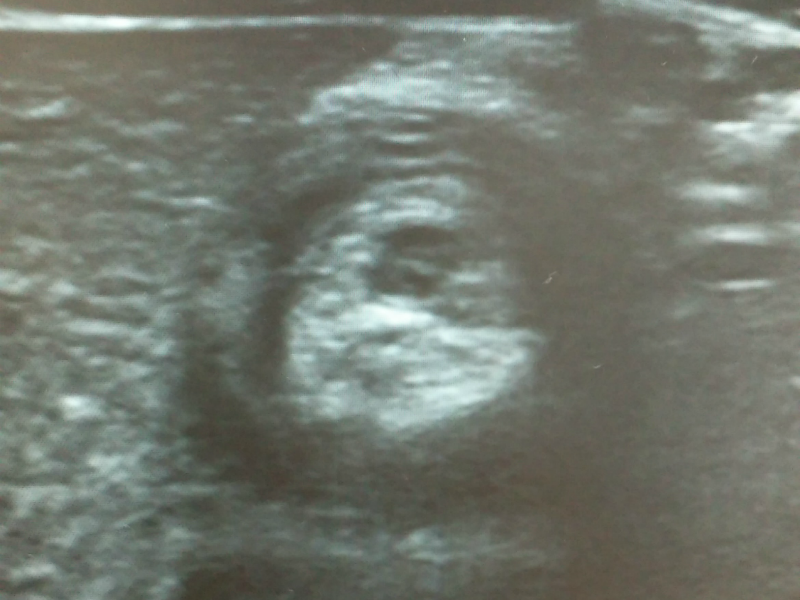

이 질환은 대부분 6개월에서 2세 사이 건강한 소아에서 갑자기 발생합니다. 보통 심하게 자지러지는 복통이 5~10분 간격으로 반복적으로 나타나는 경우가 흔하고 시간이 지나면 구토와 혈변, 그리고 젤리 같은 변을 보는 특징이 있습니다. 장벽에 있는 점액질이 함께 나오는 것이겠죠. 진단은 초음파로 장이 겹쳐져 막힌 부분을 확인하는 것이고 치료는 항문을 통해 공기나 조영 물질을 섞은 액체로 장을 밀어내어 펴주는 치료를 하게 됩니다. 간혹 관장 정복에 실패하거나 장천공이 발생하면 수술적 치료가 필요한 경우도 생깁니다.